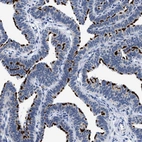

Immunohistochemical staining of human bronchus shows strong positivity in apical membrane in respiratory epithelial cells.